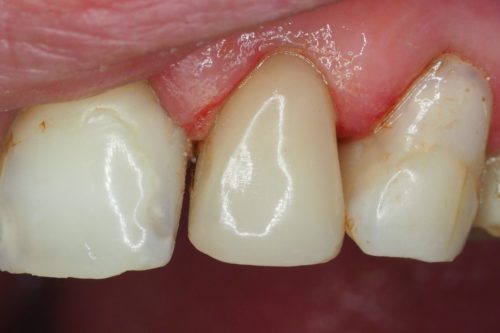

Pacjent zgłosił się z powodu brzydkich, kilkuletnich wypełnień w odcinku przednim

Dokonano wymiany wypełnień na takie z wysokoestetycznego materiału kompozytowego